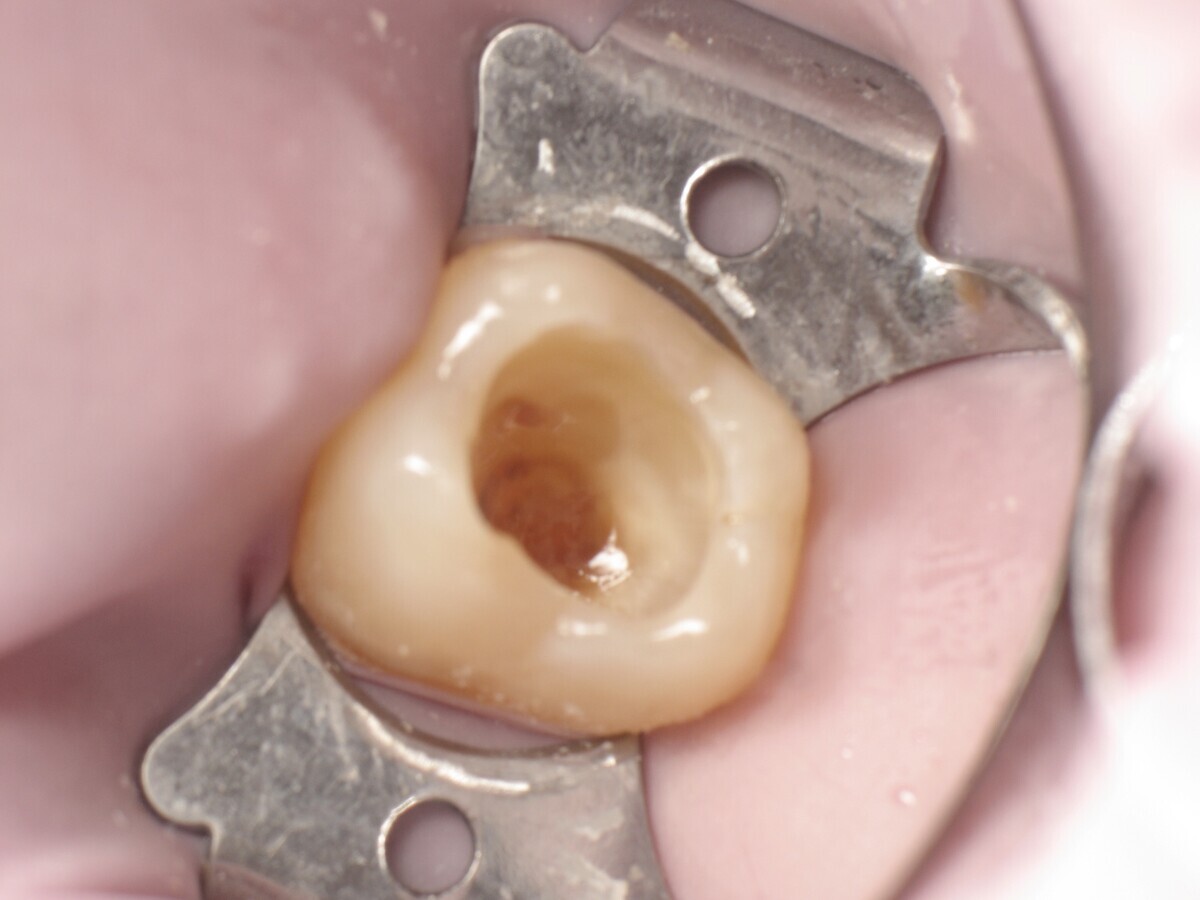

Este artículo describe el tratamiento de una cavidad clase I en un molar utilizando un composite termoviscoso mediante la técnica de la almohadilla (Figura 1). En primer lugar, se registran los detalles anatómicos utilizando una resina transparente, fluida y fotopolimerizable (Clip Flow, VOCO). El diente se aísla con un dique antes de aplicar el composite transparente a la superficie oclusal con un cepillo aplicador y fotopolimerizar durante 10 segundos (Figuras 2-4). La almohadilla oclusal así obtenida (Figura 5) debe almacenarse en alcohol (etanol o isopropanol) para eliminar la capa de inhibición. Luego se limpia la cavidad clase I (Figuras 6 y 7). A continuación se graba el esmalte durante 30 segundos y la dentina durante 15 segundos (Conditioner 36, Dentsply Sirona) y luego se enjuaga bien (Figuras 8 a 10). Debido al bajo espesor de la dentina remanente, también se aplica protección pulpar (Telio Desensitizer, Ivoclar Vivadent) (Figura 11). Luego se frota el adhesivo sobre las superficies dentales durante 20 segundos (Futurabond DC, VOCO), luego se seca bajo una pulverización de aire sin aceite graso durante 5 segundos y luego se fotopolimeriza durante 10 segundos (Figuras 12, 13). Para una humectación óptima, el fondo de la cavidad se cubre con un compuesto fluido de baja viscosidad (GrandioSO Light Flow, A3.5, VOCO) y se fotopolimeriza durante 20 segundos (Figuras 14, 15). Utilizando el Dispensador VisCalor, un dispensador portátil que permite el calentamiento y la aplicación simultánea de resinas, la cavidad se llena luego con un composite termoviscoso bulk (VisCalor Bulk, A2, VOCO).

Figura 06. Cavidad durante la excavación.

Figura 07. Cavidad después de la excavación.